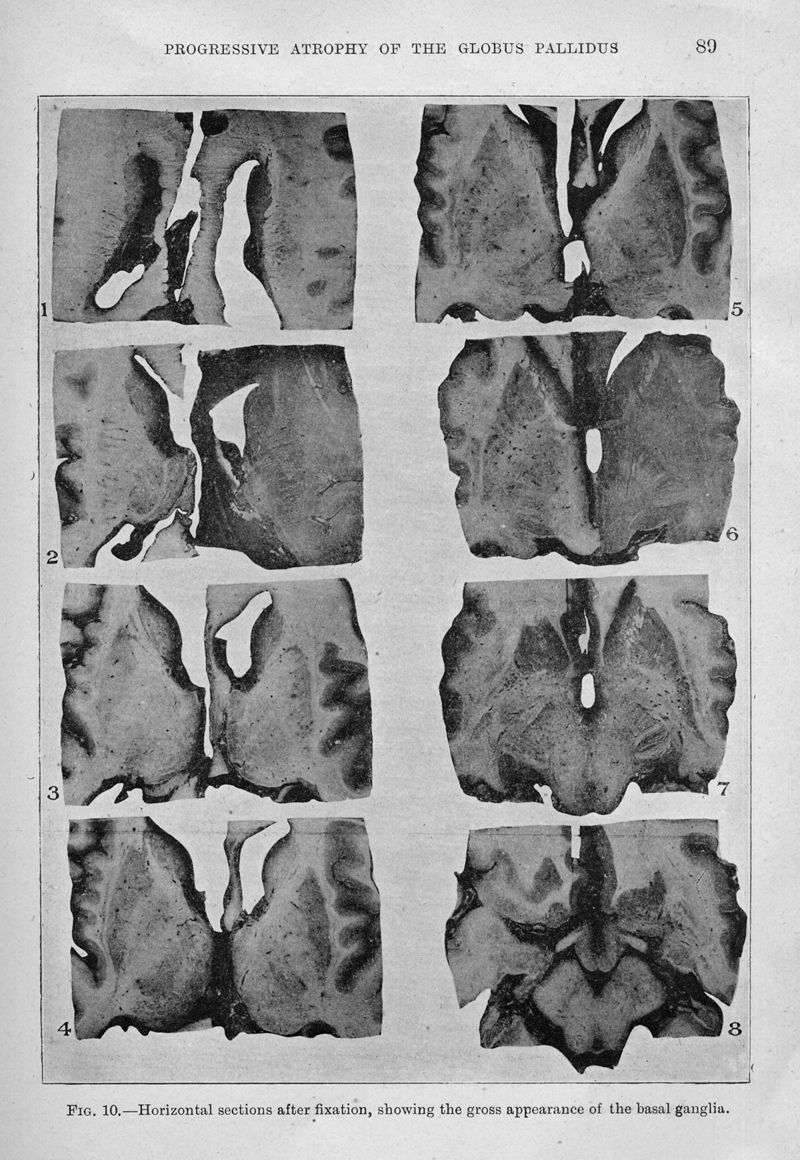

Progressive atrophy of the globus pallidus (primary atrophy of the pallidal system). A system disease of the paralysis agitans type, characterized by atrophy of the motor cells of the corpus striatum. A contribution to the functions of the corpus striatum

In : Brain (Print), 1917, Vol. 40, pp. 58-148